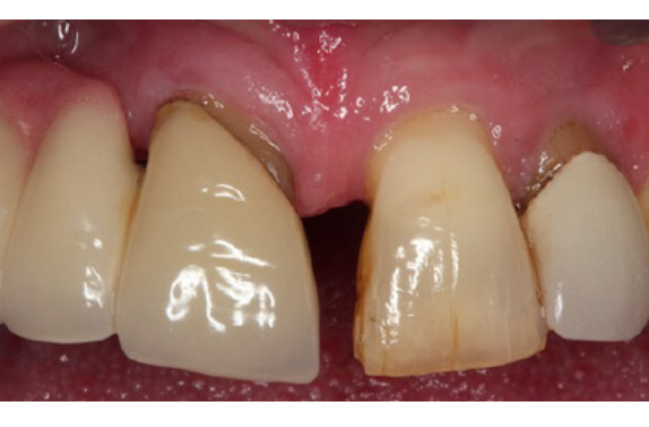

Periodontal surgery provides improved access to the roots and bone hidden under the inflamed gum. The gum is carefully peeled back to allow thorough decontamination of the root surface. Depending on the pattern of bone loss, a decision may be taken to re-contour the bone; which would allow the gum to heal in a more predictable manner.

In certain situations, there may be an opportunity to regenerate the lost bone. Bone grafting materials and special tissue stimulating proteins can be used to aid the re-growth of natural bone and improve the overall support for the tooth.